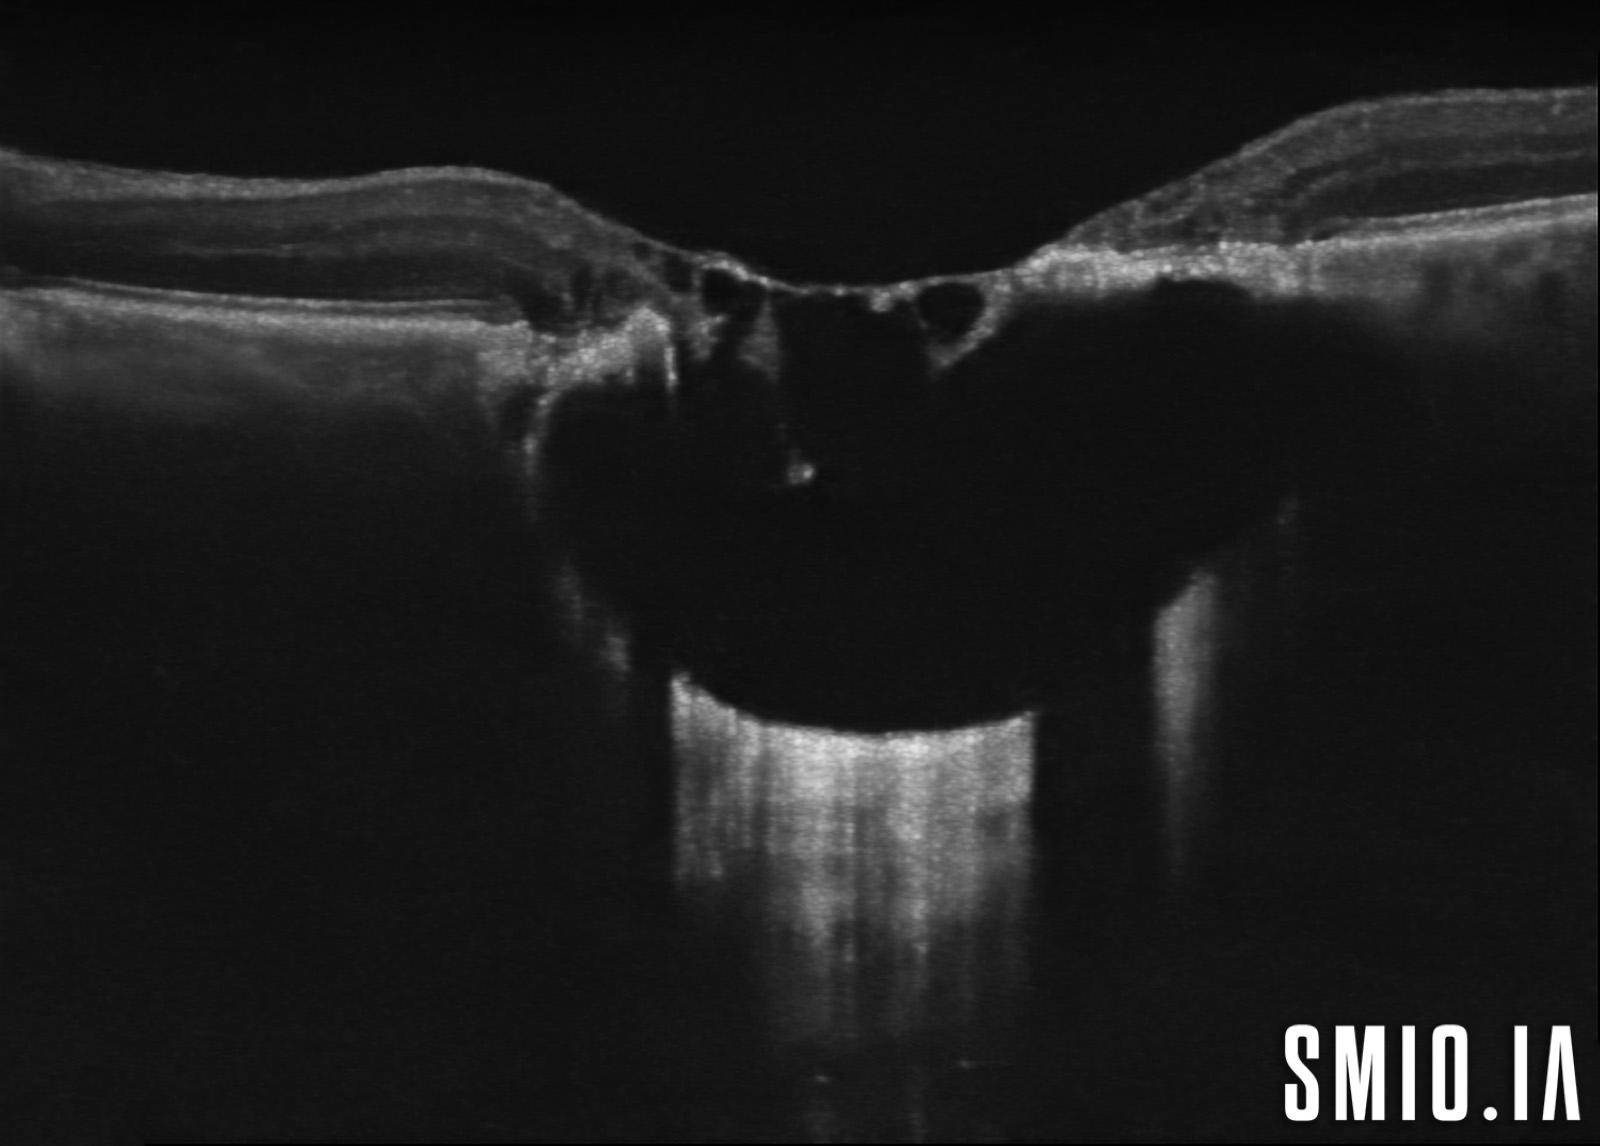

Description: L'image stéréo d'une cicatrice choriorétinienne de toxoplasmose oculaire congénitale avec l'OCT à travers la lésion a démontré une grande lésion choriorétinienne excavée de colobome avec une cavitation intrachoroïdienne